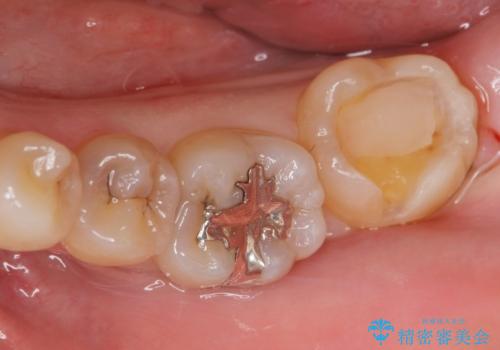

- 矯正を考えている患者様です。

歯の噛む面(咬合面)に虫歯が見られたので拡大鏡下で除去し

白い詰め物(e-maxインレー)にて治療しました。